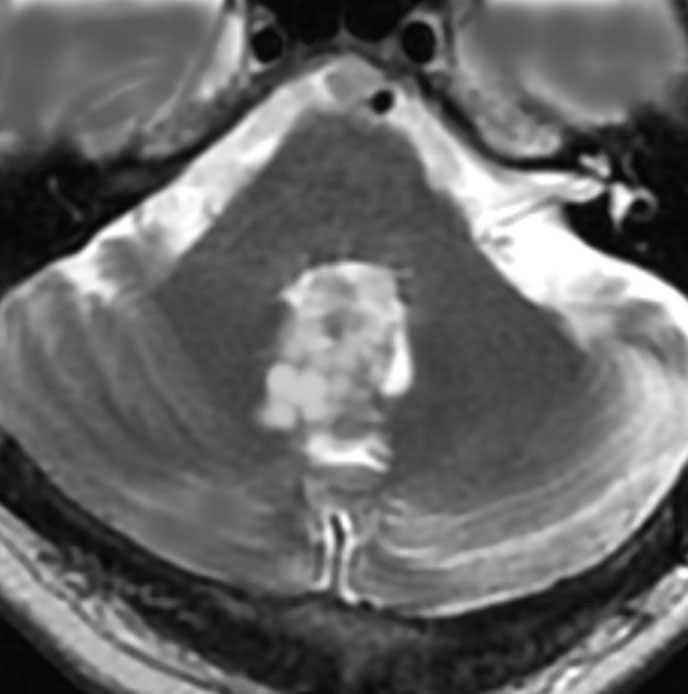

画像所見

- 比較的境界明瞭な固形腫瘍です

- T2強調画像で高信号,T1では低信号で,部分的にガドリニウム増強されます

- 小脳内の離れた部位に結節を作ることがあります

- 成人の毛様細胞性星細胞腫に似ている所見と言えます

偶然に発見された無症状の例

1990年代に無症状で発見され生検術を行った20代男性の例です。その後20年近く観察しましたが増大しませんでした。